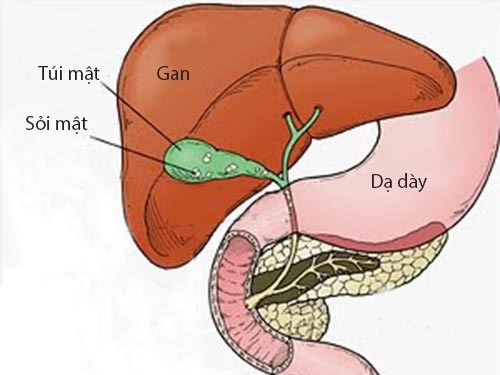

Анатомия и особенности Гартманова кармана желчного пузыря